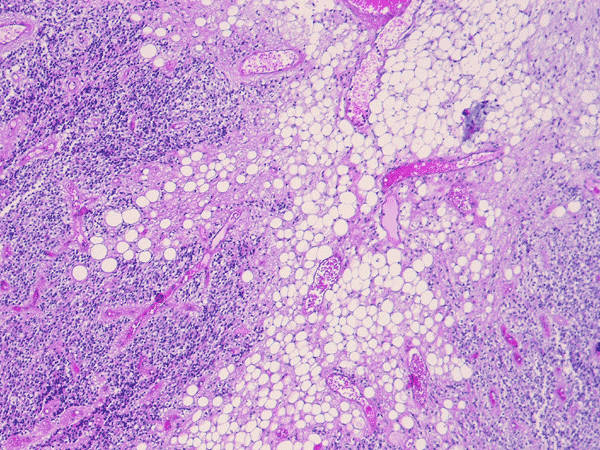

Pathology of the case:  The specimen was fragments of soft tan tissue. The lesion is a cellular neoplasm with solid sheets of cellular component admixed with irregular islands of lipidized cells with morphology of mature adipocytes (Panel A). The two components are well demarcated from each other (Panel B). The cellular component contains predominantly of polygonal cells with round nuclei and minimal nuclear pleomorphism (Panel C and D). Although a perinuclear halo is present in most of the tumor cells, the cytoplasm is not optically clear in some tumor cells and contains a amphophilic, finely granular cytopalsm. Scant amount of neuropils are present. On immunohistochemistry, the cellular component is strongly immunoreactive for syanptophysin ((Panel E).  Immunoreactivity for NeuN is weak and heterogeneous. Some entrapped reactive astrocytes are demonstrated by immunohistochemistry for glial fibrillary acidic protein but both cellular and adipose cell-like components are negative. No immunoreactivity for neurofilament proteins is demonstrated in the tumor cells.

Cerebellar liponeurocytoma have been described in the cerebellar vermis, hemispheres and as tumor that grow into the cerebellar pontine angle. Histologically, the neuronal/neurocytic component is composed of sheets of uniform polygonal cells with round nuclei. Distinct perinuclear halo similar to those being seen in oligodendroglioma and central neurocytomas are present in the neuronal/neurocytic component. This would lead to a honey comb pattern under low- or medium-magnification.  Some of these cells may also have amphophilic granular cytoplasm. Neuropil formation can be focally seen. The lipidized component is morphologically indistinguishable from mature, adult type of adipose tissue  in other part of the body. Histologic variation between different tumors do not appear to be substantial.